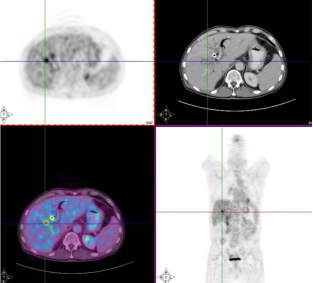

Another example is given in Figure 13. Because of potential attenuation correction artifacts, it is good practice to always make a reconstruction of the PET image without attenuation correction (Figure 13.A). This image has of course always many artifacts too, but these artifacts tend to be similar in all patients, so one can learn to read such images. Comparison of the image with and without attenuation correction may reveal subtle attenuation correction artifacts, which otherwise might lead to the wrong diagnosis. Such an artifact is present in the brain in Figure 13.C, which shows a left-right asymmetry caused by a motion artifact.

Figure 13:Coronal slice of a whole body PET/CT study reconstructed without (A) and with (C) attenuation correction based on a whole body CT (B). PET and CT are combined in a fusion image (D). The relative intensity of the subcutaneous metastasis (small arrow) compared to the primary tumor (large arrow) is much higher in the non corrected image than in the corrected one, because the activity in this peripheral lesion is much less attenuated than the activity in the primary tumor. A striking artifact in (A) is the apparent high uptake in the skin and the lungs. Note also that regions of homogenous uptake, such as the heart (thick arrow), are no longer homogenous, but show a gradient. The uptake in the left side of the brain (dotted arrow) is apparently lower than in the contralateral one in (C). The fusion image shows that the head did move between the acquisition of the CT and the emission data, resulting in an apparent decrease in activity in the left side of the brain due errors in the attenuation correction.